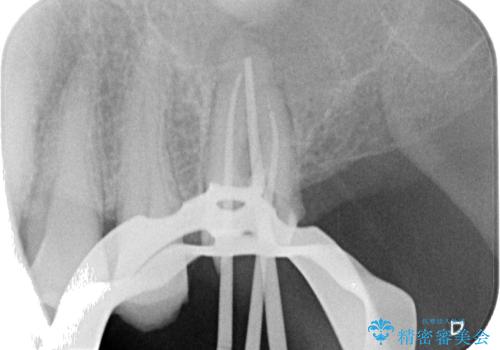

しかしながら、レントゲンやCT画像から、手前の破損したクラウンの根尖部に大きな病変が認められ、インプラント埋入部にまで病変が及んでいることから、まずは手前の根管治療を行い、病変の正体を確認した後にインプラント埋入を行うこととしました。